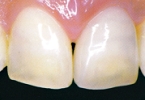

■CASE-3.(ジャケットクラウン)

[術前] [ファイバーコア築盛] [術後]